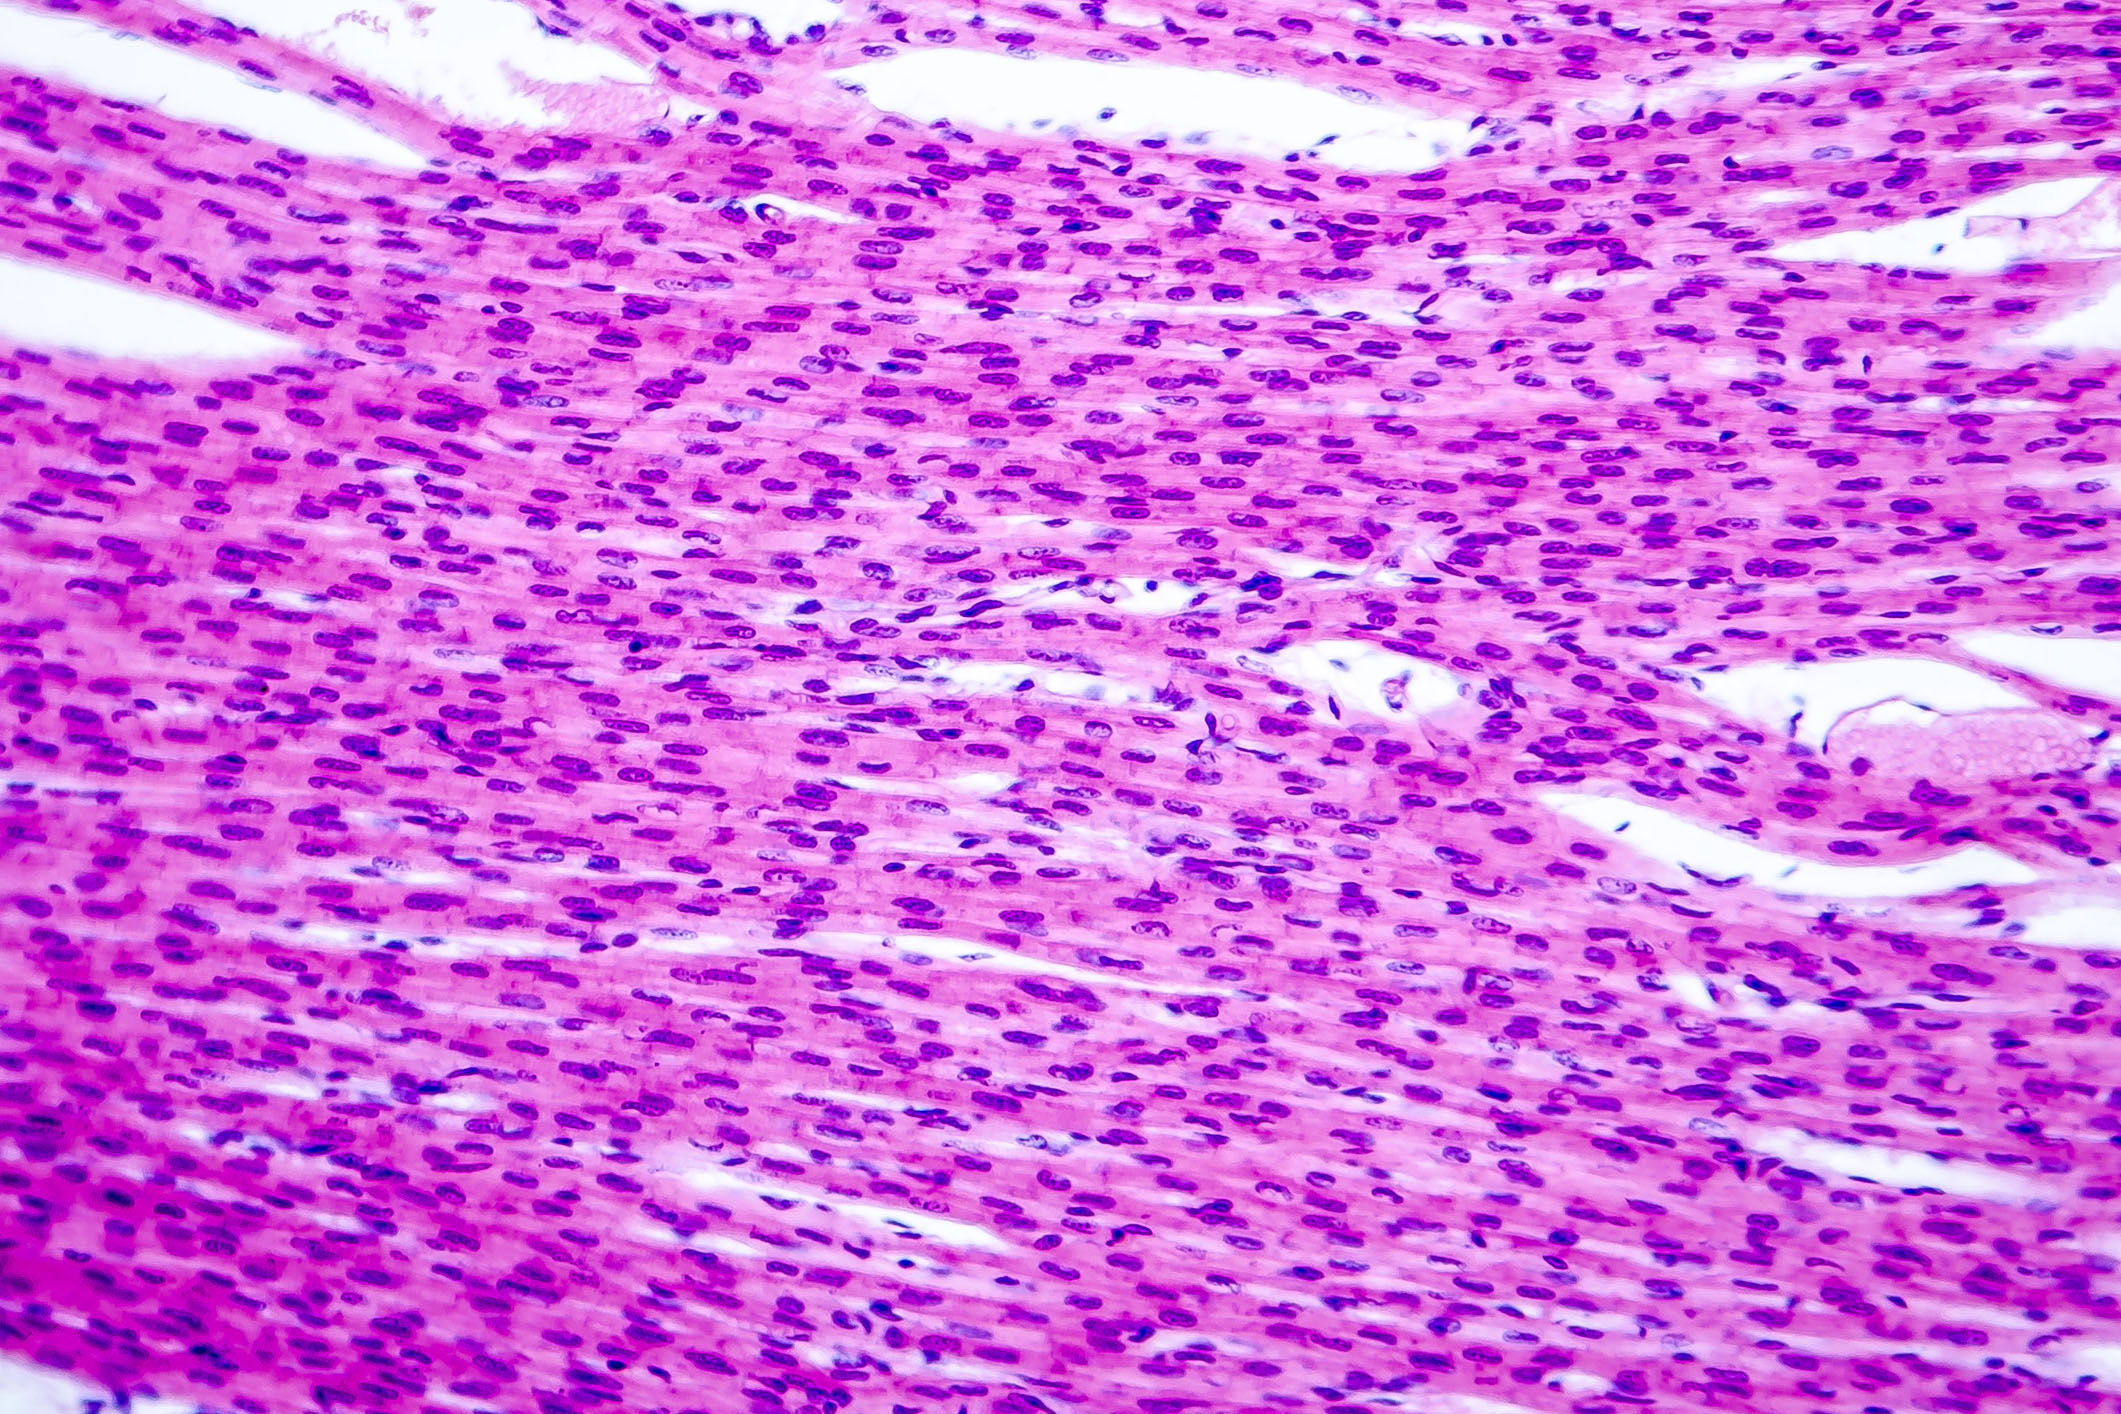

The research team analyzed blood components from healthy adults and those with heart failure. They found that ActRII activity was higher in older adults and in people with heart failure. They also found that ActRII activity was higher in heart muscle cells of mice with heart failure.

When the scientists injected young, healthy mice with activin A, ActRII was activated, and heart function declined. At the same time, there was a drop in a protein called SERCA2a, which is important for heart muscle cell function.

Next, the team tested a treatment approach for heart failure. They used a drug known as CDD866 to block ActRII. CDD866 can bind to the receptor and prevent activin A from activating it. CDD866 blocked activin A from causing a drop in SERCA2a. Inhibiting the ActRII pathway in this way improved heart function in tests with several different groups of mice with heart failure.